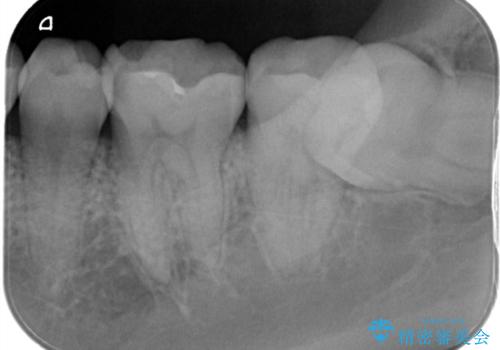

定期検診で虫歯発見。セラミック治療

- 定期検診に通われている患者様で虫歯を発見し患者様に話をしたら、治療を進めていきたいとのことだったので治療を行いました。

まずは虫歯をしっかりと取る事が大切です。

虫歯をとった後は、削った形に型を取る事で隙間なく歯にあった被せ物ができてきます。